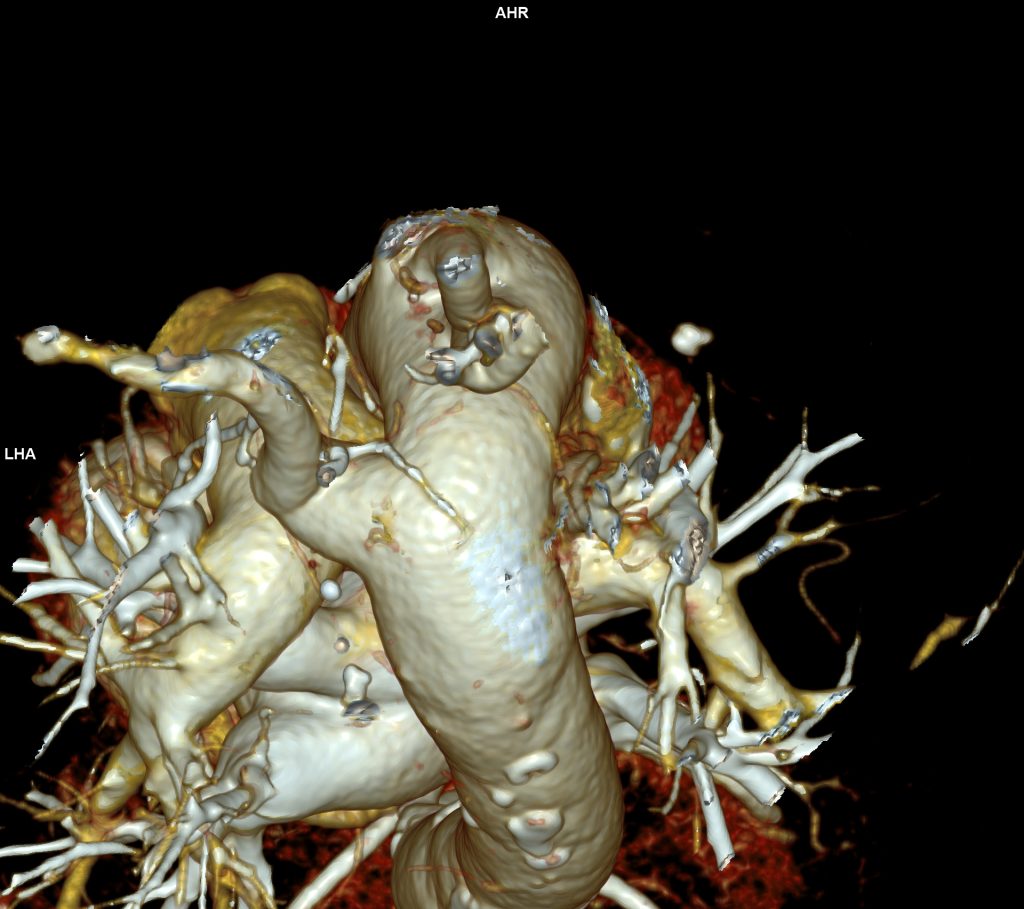

CAZ nr 57: Arc aortic de partea dreaptă si diverticul Kommerell

Figura 3, 4, 5: reconstrucție de volum 3D din achiziție angioCT toracică

Discuţie caz nr 57:  pacient asimptomatic care a efectuat angioCT de aorta toracică pentru evaluarea unei creșteri de calibru a aortei la examinarea ecocardiografica. Este o anomalie de dezvoltare a arcului aortic, ce este situat la dreapta, cu originea arterei subclavii stângi dintr-o structura diverticulară.